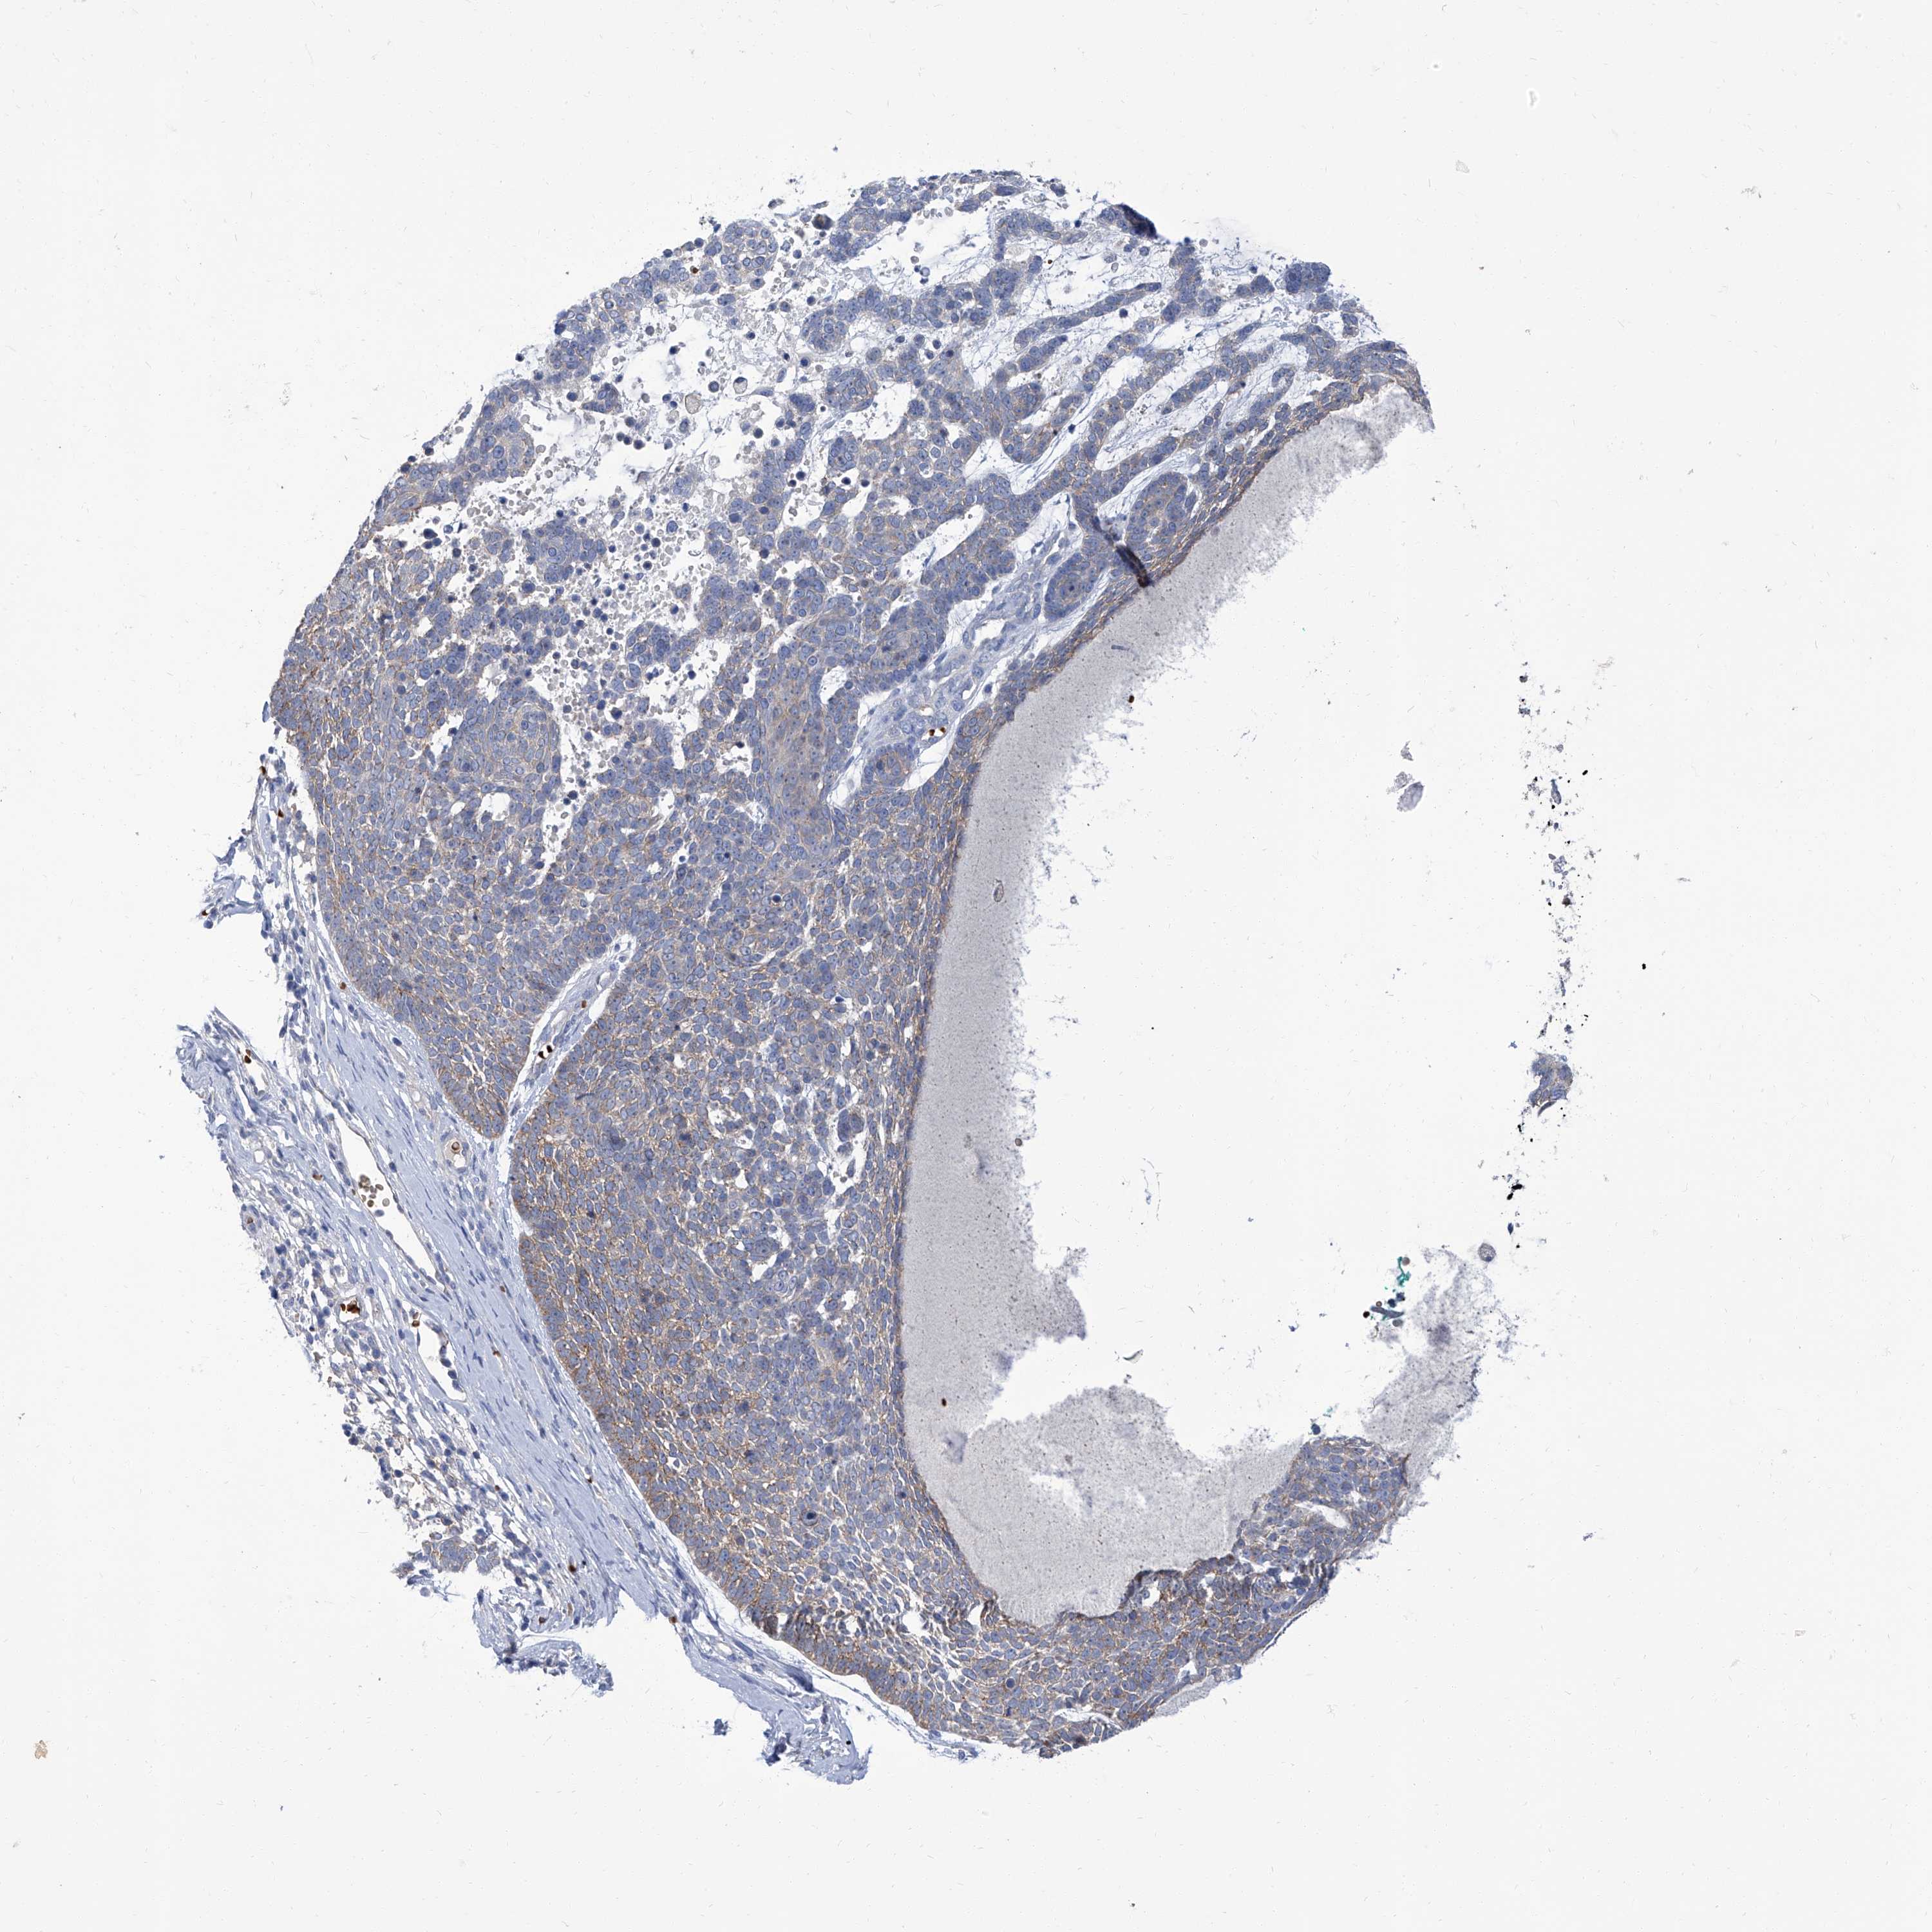

SKIN CANCER - Protein expressioni

A mouse-over function shows sample information and annotation data. Click on an image to view it in a full screen mode. Samples can be filtered based on level of antibody staining by selecting one or several of the following categories: high, medium, low and not detected. The assay and annotation is described here.

Each image is clickable and will lead to virtual microscopy that enables deeper exploration of all samples and also displays staining intensity scores, fraction scores and subcellular localization as well as patient and tissue information for each sample.

Antibody HPA030443

Staining

High

Medium

Low

Not detected

Intensity

Strong

Moderate

Weak

Negative

Quantity

>75%

75%-25%

<25%

None

Location

Nuclear

Cytoplasmic/membranous

Cytoplasmic/membranous,nuclear

Squamous cell carcinoma, NOS